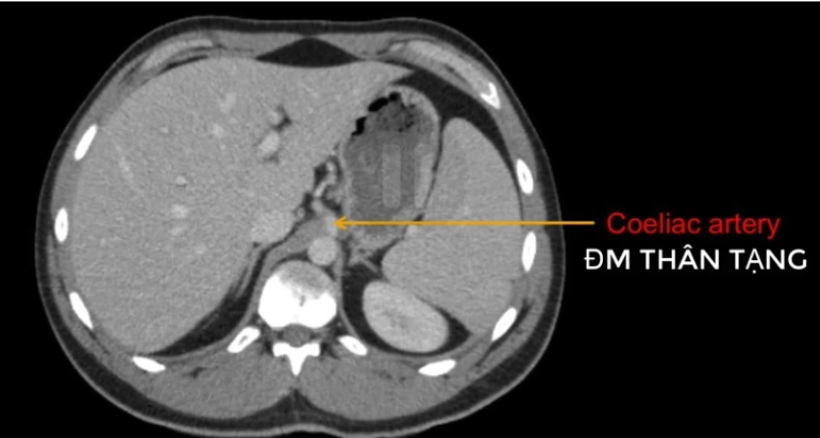

đm thận T?